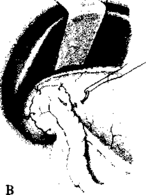

Б

Рисунок 5 - Ушивання перфоративної виразки

А – перший ряд швів через усі шари стінки; Б – другий ряд швів; В – підшивання сальника за Островським-Чухрієнко